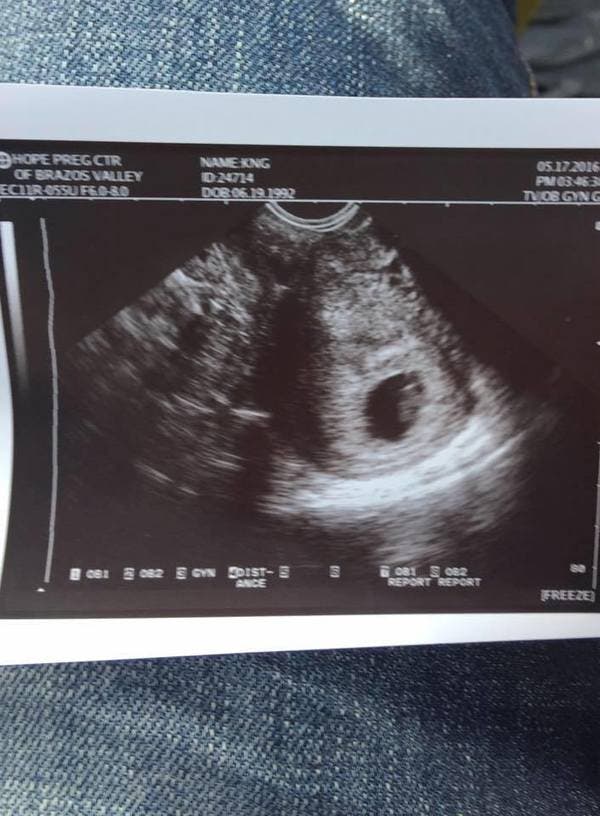

Le 1er août 2016, Kristian a fait une échographie, mais ne savait pas encore le sexe du bébé, il fallait attendre encore une semaine. Les deux tourtereaux ont donc décidé d’organiser une fête pour révéler le sexe du bébé à la famille et aux amis. La fête était prévue pour le 8 août, mais tragiquement, cette soirée n’a jamais eu lieu !